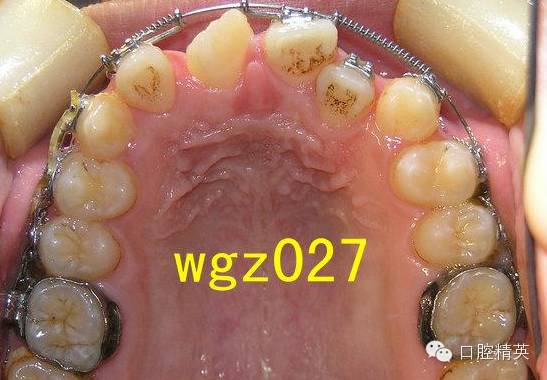

这是作者经手矫治的一位16岁男孩,牙列拥挤,磨牙远中关系,上颌中切牙(UR1)严重扭转案例。矫治前期使用了磨牙推进器推后矫治技术,开拓后牙弓间隙,调整磨牙关系。

本篇内容主要介绍该患者2期治疗阶段,上颌严重扭转中切牙经典矫治过程,希望对年轻医生,进修医生的学习及临床工作有所借鉴和帮助。